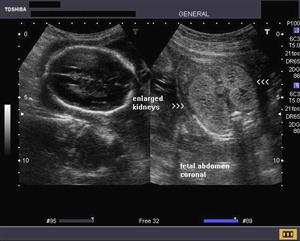

Images of Chronic Kidney Diesease

Chronic Kidney Diesease Images

Pictures of Chronic Kidney Diesease

Chronic Kidney Diesease Photos

Photos of Chronic Kidney Diesease